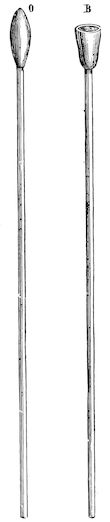

Fig. 1.—Rachitis in a young goat.